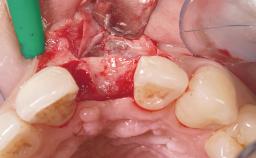

Immediate Flapless Placement of an Implant in a Maxillary Left Central Incisor Site

A 29-year-old female patient presented for treatment to replace the upper left central incisor tooth with an implant- supported restoration. The tooth had been intermittently symptomatic for the previous 12 months. The tooth had originally suffered trauma about 15 years previously. Several endodontic treatments had been performed, including an apicectomy procedure to retain the tooth. The patient was healthy and a non-smoker. She had reasonable expectations in regard to esthetic outcomes and the risk of marginal tissue recession following treatment. At medium smile, the gingival margins of the upper teeth were visible, with a display of 3 to 4 mm of the gingival margins. Gingival recession of tooth 21 and a discrepancy in the gingival levels between teeth 11 and 21 was observable during normal speech and smile.

| Placement Protocol | Immediate implant placement |

| Tooth Site | Maxillary incisor or canine |

| Socket Integrity | Damage to one or more bone walls |

| Bone Volume | Damage to one or more socket walls |

| Risk of Complications | High |